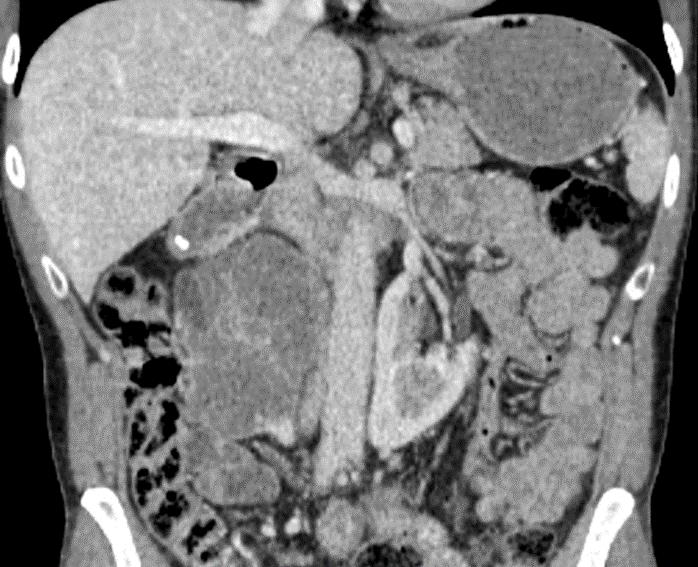

Souhrn: Cíl: Mikrovlnná ablace představuje v léčbě cT1 renálních karcinomů alternativu k resekčním výkonům. Cílem naší studie bylo retrospektivně zhodnotit onkologické výsledky a pooperační komplikace této metody. Soubor pacientů: Retrospektivní unicentrická studie obsahuje 63 pacientů, kteří podstoupili celkem 78 mikrovlnných ablací na našem pracovišti mezi lety 2012 a 2023. Výsledky: Studie prokázala výraznou vazbu onkologických výsledků na velikost tumoru. U pacientů s tumorem < 3 cm zůstalo po dobu sledování bez recidivy 86 % pacientů, v případě tumorů > 3 cm nemělo recidivu 68 % pacientů. Pooperační komplikace se vyskytly u 18 % pacientů, přičemž u 6 % pacientů se jednalo o komplikace závažné (stupeň ≥ 3 dle Clavien-Dinda). Závěr: Mikrovlnná ablace v léčbě lokalizovaných nádorů ledvin (cT1) představuje moderní a bezpečnou miniinvazivní techniku. Terapeutický výsledek je výrazně závislý na velikosti tumoru. U tumorů do 3 cm dosahuje metoda srovnatelných onkologických výsledků s podobnou frekvencí výskytu pooperačních komplikací jako resekční výkony.

Renální karcinom (RCC – renal cell carcinoma) je v České republice časté onkologické onemocnění dosahující incidence 3 100 případů za rok. Onemocnění je diagnostikováno nejčastěji mezi 65. a 74. rokem věku, přičemž u mužů je 1,7× častější. Ročně na RCC umírá přibližně 650 mužů a 390 žen [1]. Diagnostika RCC se zakládá především na zobrazovacích metodách (sonografie, CT vyšetření, výjimečně magnetická rezonance). Vzhledem k často asymptomatickému průběhu onemocnění v počátečních stadiích se často jedná o incidentalomy. V případě lokalizovaných tumorů ve stadiu cT1, tedy tumorů do 7 cm v největším rozměru, které jsou předmětem naší studie, je upřednostňovanou metodou léčby resekční výkon [2]. Optimální volbou je resekce ložiska, popřípadě nefrektomie u případů, u kterých uložení tumorózního ložiska resekci neumožňuje. Nicméně u polymorbidních pacientů, pro něž by byla celková anestezie vysoce riziková, či u pacientů se sníženou funkcí ledvin, u nichž by radikální výkon mohl vést k významné renální insuficienci, existují alternativy v podobě aktivního sledování, pozorného vyčkávání či miniinvazivních ablačních metod. Tyto varianty mohou zvolit i pacienti, kteří si velký chirurgický zákrok nepřejí [3–5]. Ablační metody lze na základě mechanizmu destrukce nádorové tkáně rozdělit na radiofrekvenční ablaci (RFA), kryoablaci a mikrovlnnou ablaci (MWA – microwave ablation).

Obr. 1. Perioperační CT snímek během MWA.

Fig. 1. Perioperative CT scan during microwave ablation.

Soubor pacientů a metody Objektem studie je soubor pacientů, kteří mezi lety 2012 a 2023 podstoupili ve FN Bulovka perkutánní MWA pod CT kontrolou pro základní diagnózu RCC. Data byla sebrána retrospektivně.

Výkon byl prováděn mikrovlnným systémem Solero Microwave Tissue Ablation System (AngioDynamics, Inc., USA). Během ablačních výkonů byla používána frekvence 2,45 GHz a výkon v rozsahu 100–140 W. Jako aplikátor byla používána nerezová ocelová jehla s keramickým hrotem o průměru 15 G a délce 14, 19 nebo 29 cm. Jedna ablační sekvence po zavedení jehly do tumoru trvá 4–6 min podle velikosti nádoru, v průběhu jednoho výkonu jsou standardně prováděny 1–2 ablační sekvence. Maximální velikost ablační zóny udávaná výrobcem je 54 × 39 mm na jednu sekvenci. Po skončení ablace tumoru se během vytahování jehly provádí ablace-koagulace punkčního kanálu (track ablace). Výkon je prováděn v analgosedaci za přítomnosti anesteziologa, pacienti snášejí výkon dobře. Celková doba výkonu vč. polohování pacienta a přípravy CT pracoviště je 60–90 min (obr. 1).